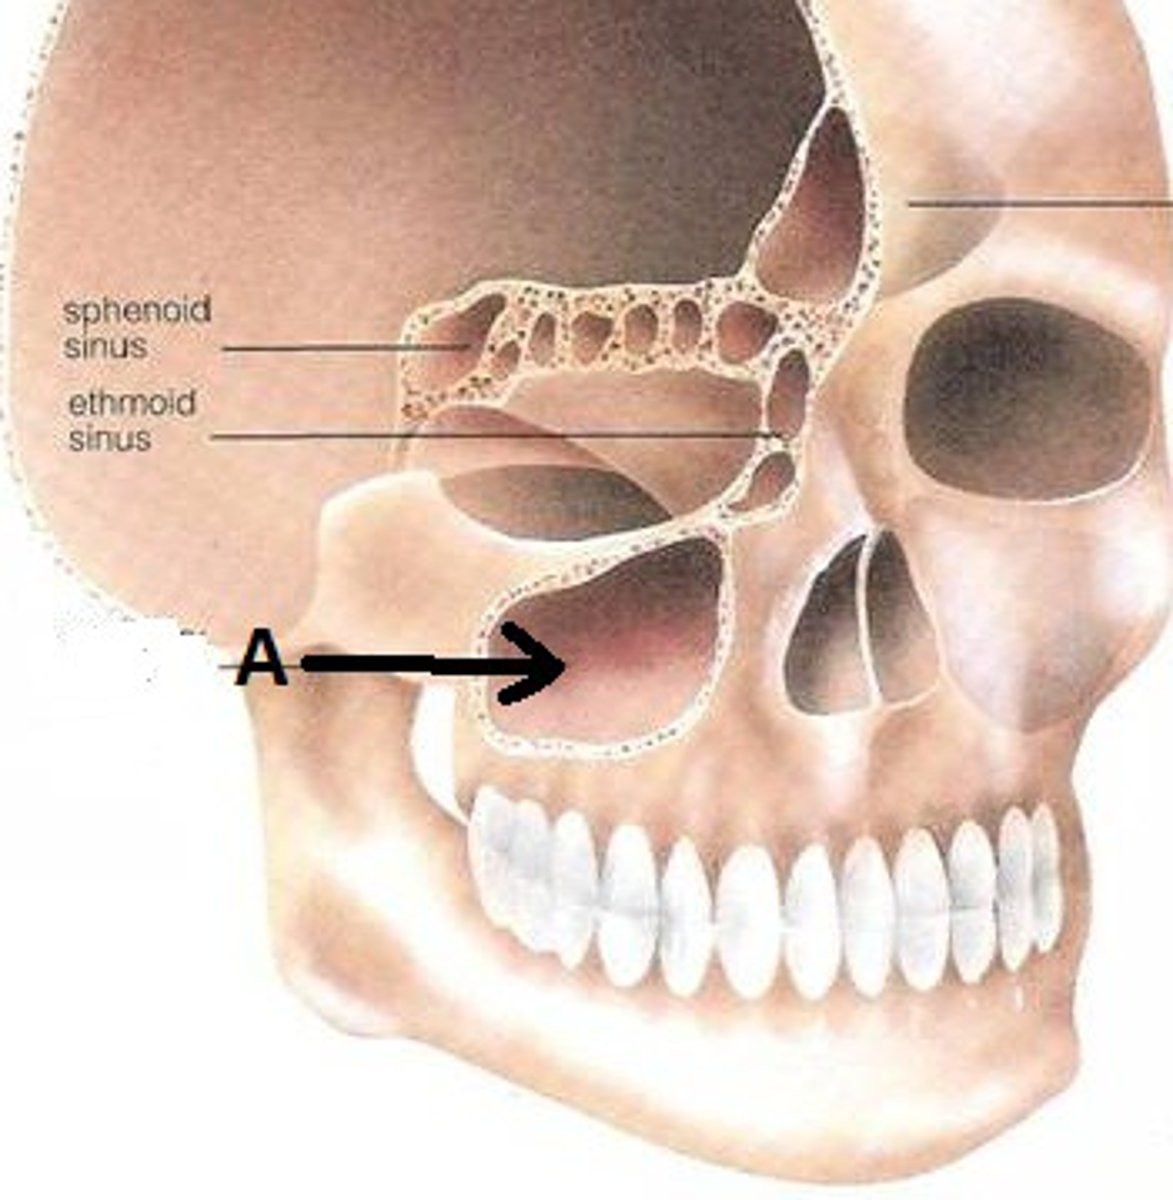

maxillary sinus

frontal sinuses

What is 4?